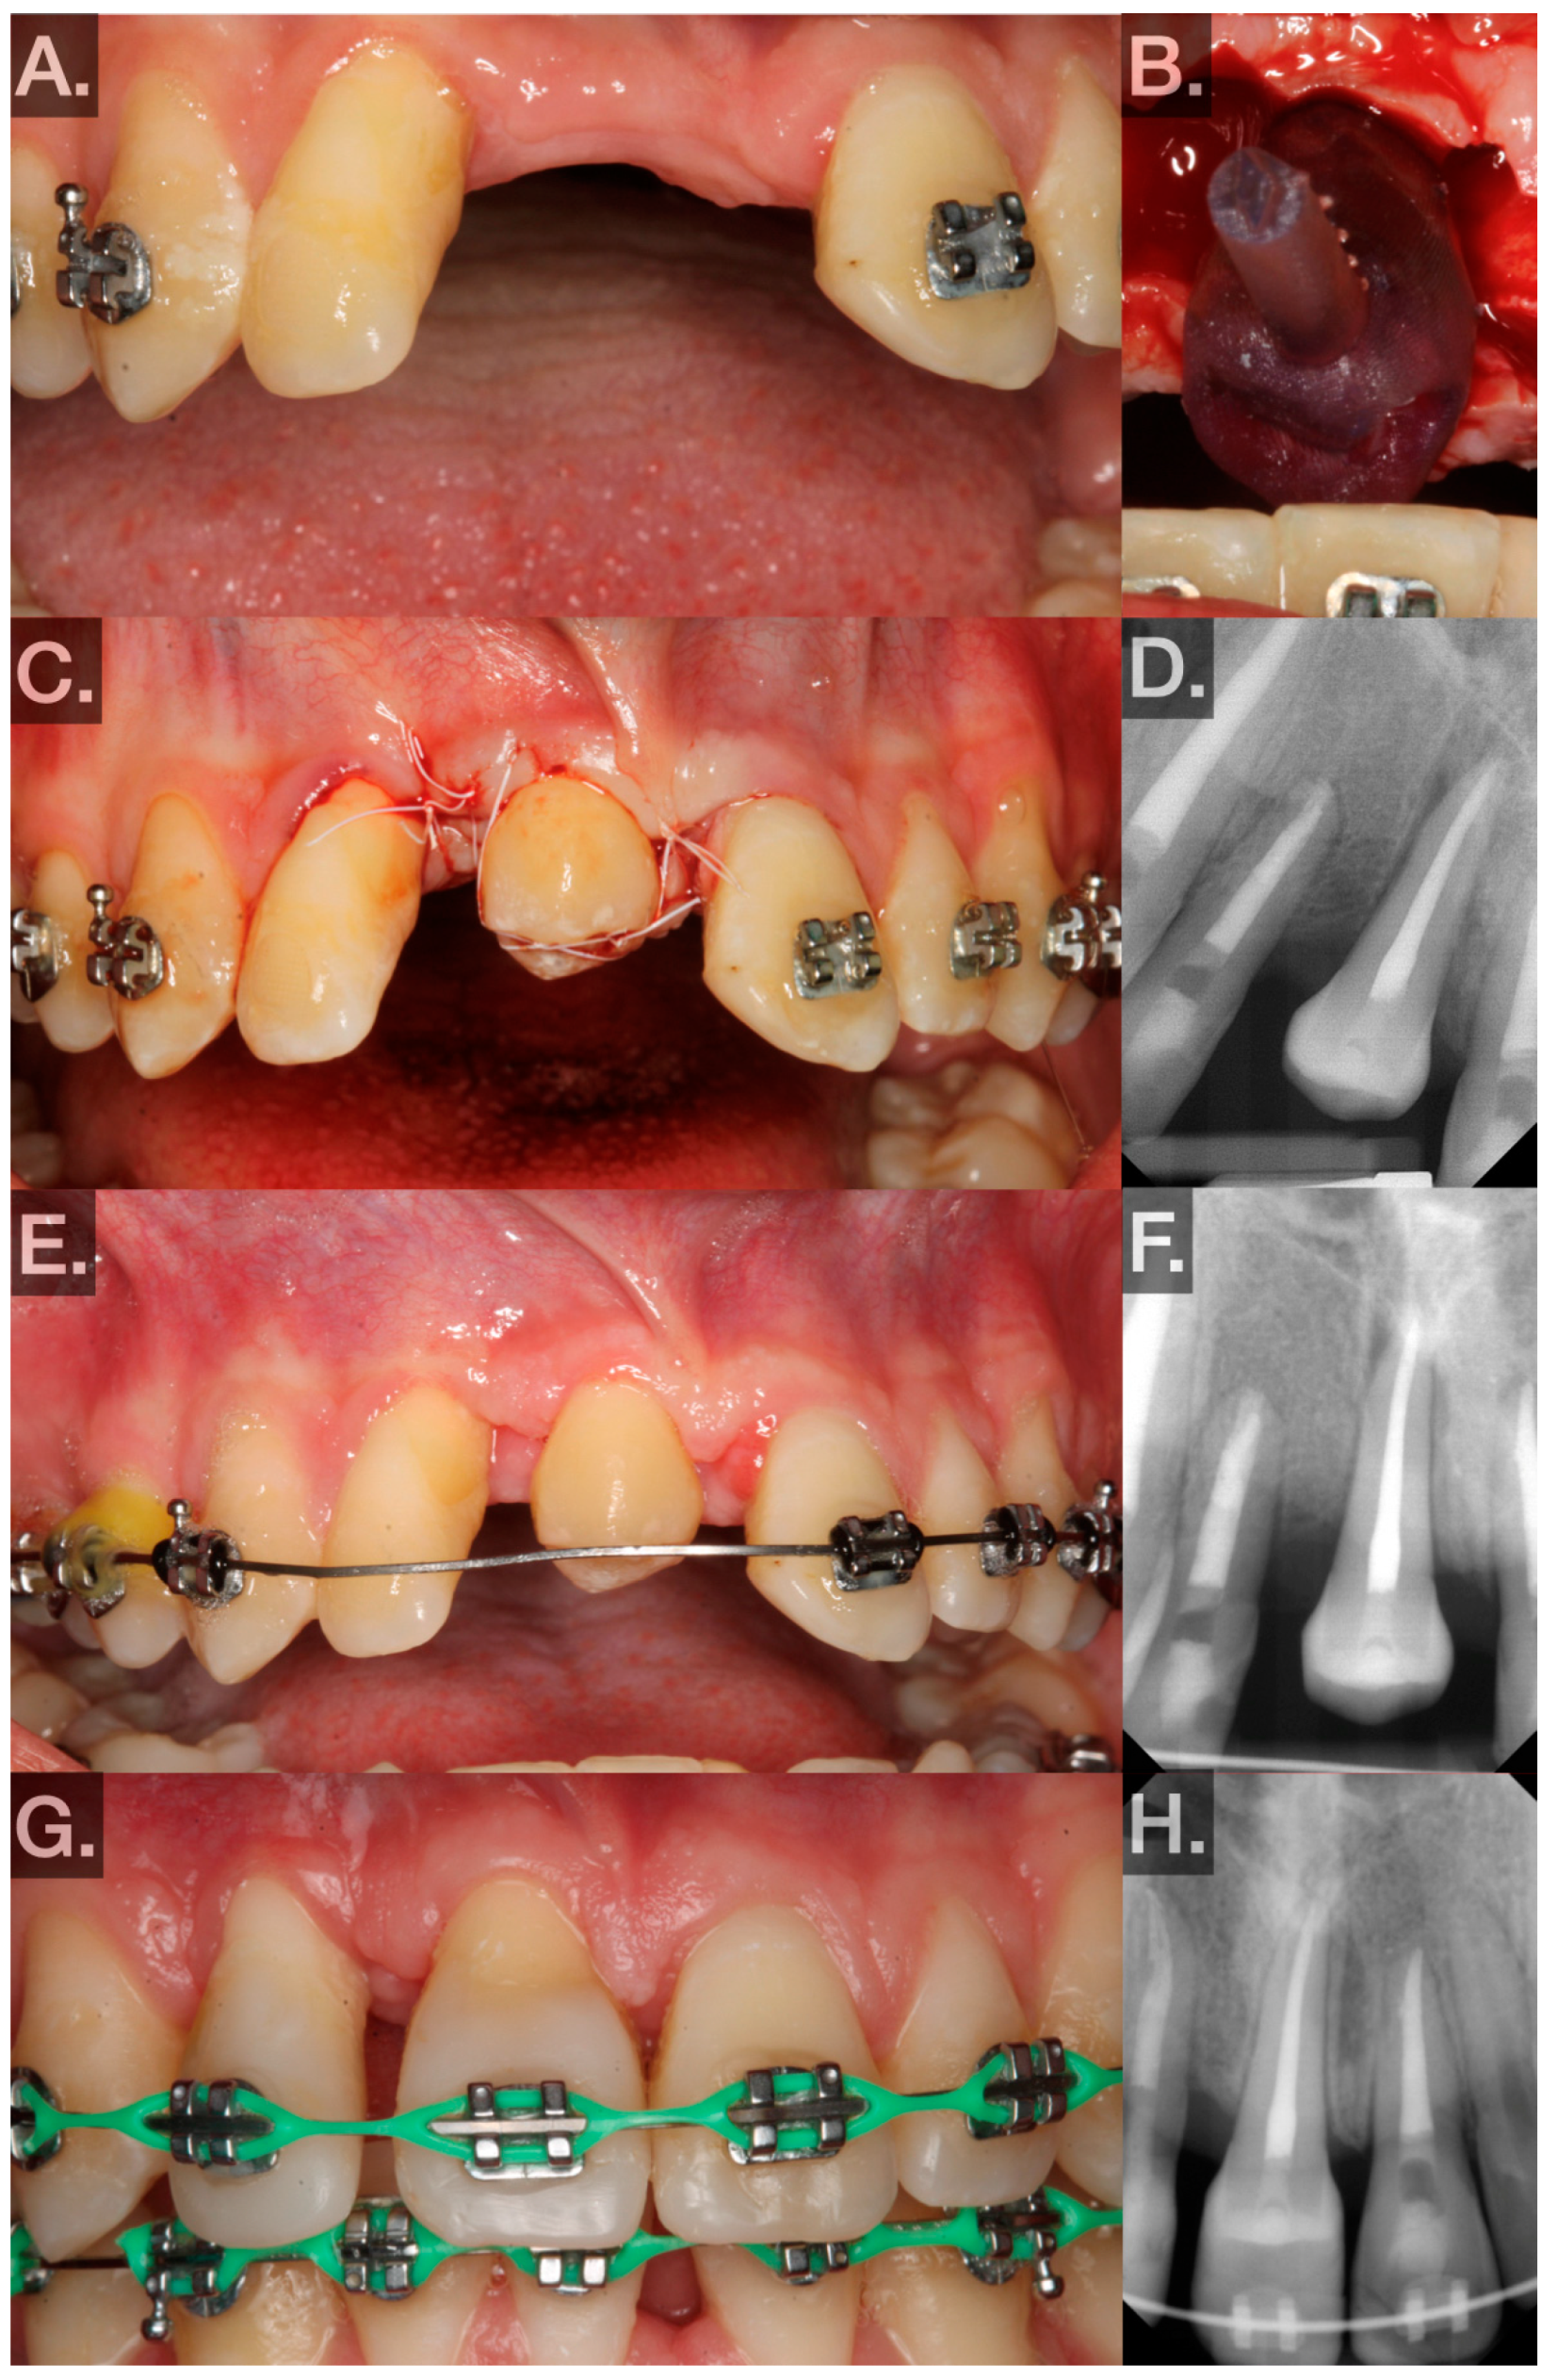

No. 24 (FDIn no. 31) → no. 7 (FDIn no. 12) (Figure 3A–H; 9/2023):

First, 1.5 carpules of Septocaine® (articaine hydrochloride 4% and epinephrine 1:100,000; Septodont, Saint-Maur-des-Fossés, France) were used to anesthetize the donor tooth and recipient sites through local infiltration. Midcrestal and sulcular incisions were made and a full-thickness flap was elevated around tooth no. 7 (FDIn no. 12). The tooth was then extracted using elevators and forceps. The extraction socket was widened using an implant motor (Implant 900, Denstply Sirona, Charlotte, NC, USA) and implant drills (Bone Level Tapered Drills, Straumann AG, Basel, Switzerland). The osteotomy was prepared to be slightly larger than the measurements made on the CBCT. After the recipient site was prepared, the replica of the donor tooth was tried in. Passive fit and subocclusal positioning were verified. Luxation forces were made with forceps on tooth no. 24 (FDIn no. 31) using slow rotational movements only. Special care was taken to ensure the beaks of the forceps did not sit apical to the CEJ. Tooth no. 24 (FDIn no. 31) was extracted atraumatically and immediately placed into the artificially created socket after a photograph was taken to demonstrate the intact PDL (Figure 3B). The extra-alveolar time was less than 30 s. The tooth was fixated in the recipient site with 4–0 polytetrafluoroethylene (Cytosurg® PTFE, Salvin, Charlotte, NC, USA) sutures via a Laurell–Gottlow suture technique [22]. Because of the small occlusal surface area, composite resin (Filtek™ Supreme Flowable Restorative, 3M™, Saint Paul, MN, USA) was bonded to the tooth to hold the suture in place. Simple interrupted sutures were also used to approximate the tissue interproximally (Figure 3C). A periapical radiograph was then taken as a baseline for evaluating healing (Figure 3D).

At week 3, bleeding on probing (BOP), probing depth (PD), and mobility were measured at 6 sites to evaluate periodontal healing (Figure 3E). The patient was instructed to resume normal brushing and to use the tooth in normal function.

• The 3-week postoperative photograph and radiograph for transplant no. 24 (FDIn no. 31) is shown in Figure 3E,F.

At week 6, BOP, PD, and mobility were measured at 6 sites to evaluate periodontal healing.

• The 6-week postoperative photograph and radiograph for transplant no. 29 (FDIn no. 45) is shown in Figure 2E,F.

At every visit, oral hygiene instructions were reinforced, mobility was checked to rule out ankylosis, and periapical radiographs were taken to evaluate periodontal healing radiographically (Figure 2F,H and Figure 3F).

Intraoral photographs and radiographs at the most recent postoperative visit (transplant no. 29 (FDIn no. 45): 10 months, transplant no. 24 (FDIn no. 31): 6 months) are illustrated in Figure 2G,H and Figure 3G,H.

Figure 3. (A) Preoperative photo showing tooth no. 7 (FDIn no. 12) with mesial attachment loss. (B) Donor tooth no. 24 (FDIn no. 31) and its PDL after atraumatic extraction and before being transplanted. (C) Transplanted no. 24 (FDIn no. 31) fixated subocclusally with sutures in the no. 7 (FDIn no. 12) site. (D) Immediate postoperative radiograph. (E) Three-week postoperative photo showing the transplanted tooth gently probed with a UNC 15 probe. (F) Three-week postoperative radiograph. (G) Six-month postoperative photo showing the transplant restored to ideal contours. (H) Six-month postoperative radiograph.